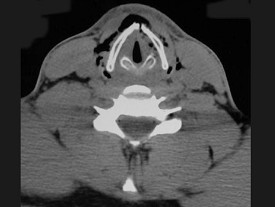

11.27岁男性,开车外出在高速行驶时翻车,呼吸困难,喉部肿胀,CT检查如图所示,请选择正确的描述或诊断 ( )![]() ![]() ![]() ![]() |

| 正确答案:ABCE |